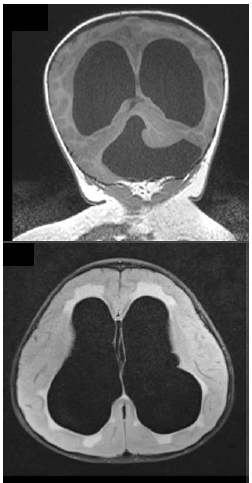

Existem diversos tipos de malformações congênitas do cérebro; muitas delas resultam em complicações motoras, sensoriais e intelectuais.

As imagens correspondem à síndrome de: